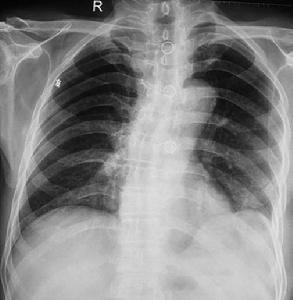

(1)影像學檢查對診斷極有幫助。X 線胸部透視或攝片可見:膈肌升高,膈上胸腔內可見實質性腫塊(如大網膜)或空腔陰影(胃泡或腸袢)等異常影像,心臟及縱隔向健側移位,右側膈肌破裂可見凸入右側胸腔的陰影等;經鼻腔置入胃管,可見胃管進入膈上胃泡內,口服或胃管內注入造影劑可證實胃在胸腔內。對於間歇期或慢性期病人可行上消化道鋇餐或鋇灌腸造影檢查,CT 掃描檢查對於確定膈疝的位置及疝入胸腔臟器的性質極有幫助。此外,X 線人工氣腹造影和B 超檢查亦有助於診斷。

(1)胸部透視或平片:X 線透視或平片檢查是創傷性膈疝最可靠、最普遍的診斷方法。一些裂口較小並被肝臟、大網膜堵塞或疝入臟器極少者,早期的胸片可能正常或基本正常,但隨著病情進展,75%的病人可有異常改變。其常見的異常X 線改變有:①左側膈肌升高;②膈肌水平之上出現異常陰影,如胸腔內出現胃腸道陰影、胃泡、腸道氣液平面或緻密陰影;③心臟、縱隔影像向健側移位;④肺萎陷、盤狀肺不張;⑤患側胸內出現液平面;⑥部分病人可有肋骨骨折徵象。由於疝入胸腔的腹腔臟器不同,創傷性膈疝的X 線表現比較複雜:A.膈肌裂口大、胃突入胸腔者,有時可表現為假膈肌升高影像。但只要透視檢查或閱片時仔細辨明脾臟和結腸脾曲的位置,一般能明確膈肌真正位置及有無膈疝的發生;B.疝入的臟器為橫結腸並發生嵌頓和絞窄時,膈下可因結腸的擴張積氣而出現類似胃泡的影像,應與胃泡相鑑別。通常結腸擴張積氣形成的假胃泡影距膈肌較遠,而真正的胃泡影緊靠膈下;C.右側膈肌破裂肝臟疝入右胸腔,X 線徵象有3 種類型。Ⅰ型:整個肝臟疝入胸腔,肝臟膈面呈一高位平滑弓形影像,與右半膈肌升高相似,極易誤診為膈膨升。Ⅱ型:肝臟部分疝入右胸腔,右膈上方有一凸出的影像。Ⅲ型:除肝臟外尚伴有胃腸部分疝入右胸腔,其X 線徵象除肝臟陰影外尚有胃、腸道的影像,並有不同程度的肺不張和胸腔積液。